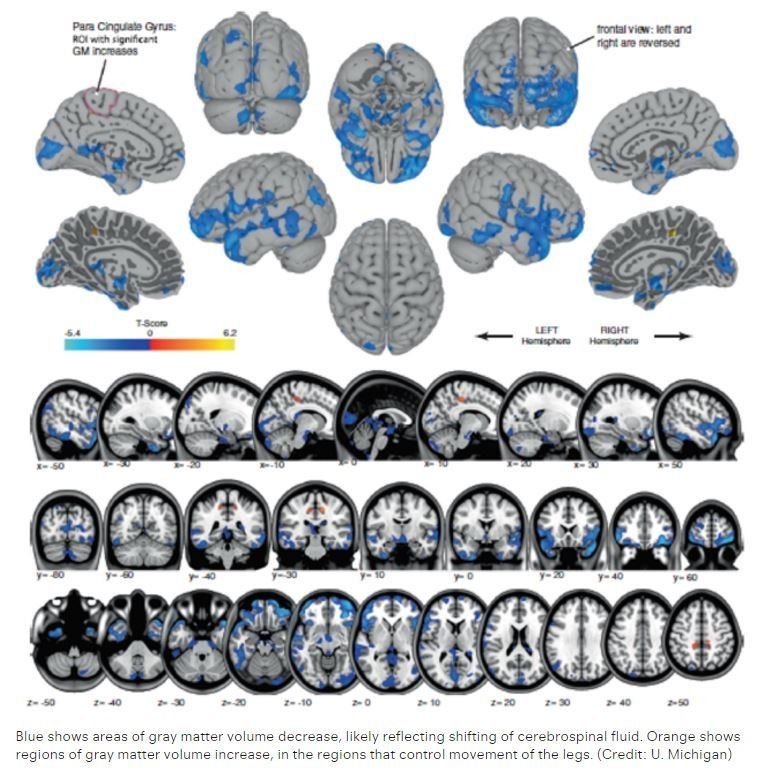

Astronauts’ brains change shape when they go into space http://wef.ch/2lFhNzX pic.twitter.com/xVkHNBDDZo